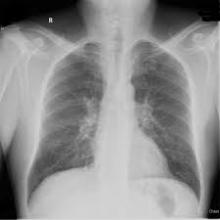

Už první návštěva „plicaře“ v malém městě kousek od bydliště mých rodičů ukázala, že toto vyšetření má smysl. Lékař se zkušeným okem podíval na můj rentgen plic a oznámil: „Máte fibrózu, objednám Vás do nemocnice na důkladné vyšetření.“

Stála jsem jako opařená a vůbec netušila, co se to děje. Neměla jsem strach, protože jsem ani ve snu netušila, co to je fibróza! „A co to jako je, pane doktore?“ ptám se. „To je něco, jako tvrdnutí plic, musím Vám nasadit kortikoidy.“ „Ale já kojím!“ „Domluvte se tedy na dalším postupu v nemocnici.“

V nemocnici mě čekala sonda do plic. Vyšetření, u kterého maté pocit, že vydávíte v nejlepším případě pouze plíce, ale spíš celé vnitřnosti. Nicméně sonda potvrdila původní diagnózu a ortel zněl: Nevyléčitelná nemoc plicní fibróza, ke stabilizaci nemoci nutno nasadit kortikoidy.

V ordinaci po zhlédnutí nového rentgenového snímku, mi lékař oznámil, že mám v levém rohu plíce pneumotorax. Laicky řečeno, plíce praskla. Proto ty záchvaty kašle. Okamžitě zvedá telefon a sanitka mě s blikajícím světlem převáží do nemocnice.